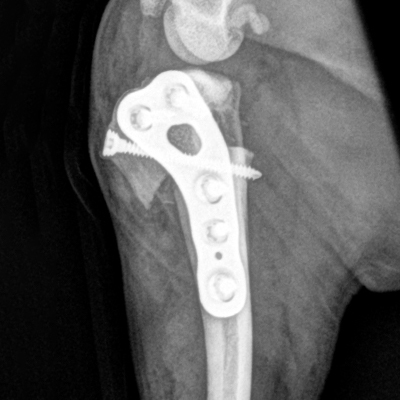

The RITA LEIBINGER Titanium TTA RAPID® Tiny, 2.0/2.4 TPLO and Titanium TPLO Swing, and our 2.0/2.4 Titanium CBLO implant systems and instrumentation are specifically designed for small patients, and can help overcome these challenges. They are typically smaller in size and have different geometries to accommodate the smaller bone structure of small dogs and cats.